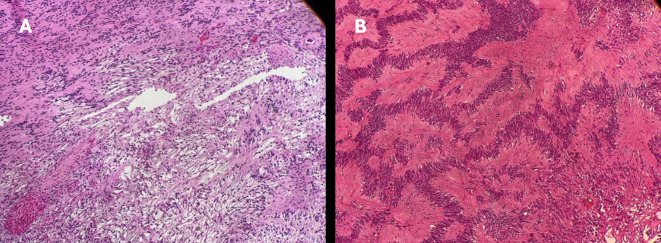

Orbital schwannomas are benign tumors that arise from Schwann cells in the peripheral nerves in the orbit. They typically present after the second decade of life given their slow growth and rarely before then. Diagnosis is based on clinical course and specific imaging modalities; however, the definitive diagnosis is by lesion biopsy. Surgical removal is typically curative. Herein we present the case of an 8-year-old boy with proptosis and diplopia where he exhibited the clinical findings of an orbital mass, however, the characteristic picture of orbital schwannoma was observed on imaging yet found within the inferior rectus muscle, a rare finding indeed.